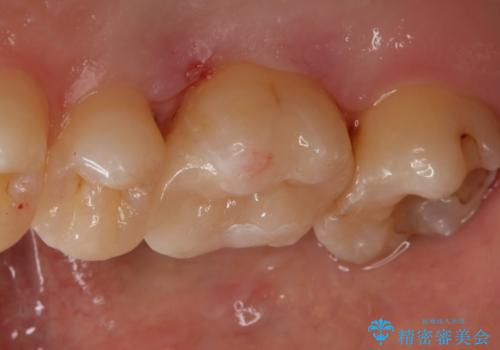

- 右上6番の銀歯をセラミックに変えたいと希望された患者様です。

切削量、形態を考慮し、セラミックインレーでの治療を計画しました。

銀歯と虫歯を除去した上でCRで裏層し形態を整えて印象を行っています。